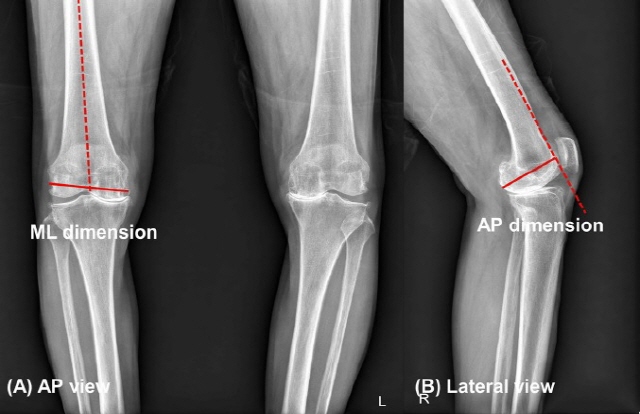

퇴행성 관절염 무릎의 수술 전 X-ray에서 대퇴골 모양 파악을 위한 가로 및 세로 길이 측정. 왼쪽부터 대퇴골의 가로길이 측정법, 대퇴골의 세로 길이 측정법./사진=강북삼성병원

연구팀은 표준형 치환물과 협소형 치환물 중 각각 치환물에 적합한 환자 군을 예측하기 위해 2018~2020년에 수술한 504례의 무릎 인공관절 전치환술 환자를 분석했다. 먼저 연구팀은 수술 전 시행한 무릎 X-ray 검사에서 환자 대퇴골 원위부의 모양을 파악하기 위해 가로, 세로 길이를 측정해 비율을 확인했다. 이어 표준형 대퇴골 치환물을 사용한 환자 대퇴골 가로-세로 비율과 협소형 치환물을 사용한 환자 대퇴골 가로-세로 비율의 차이를 분석했다. 그 결과 환자 대퇴골 가로 세로 길이의 비가 133.3%~135.4% 이하인 경우, 표준형 대퇴골 치환물을 사용했을 때 돌출 발생 위험성이 증가했다.